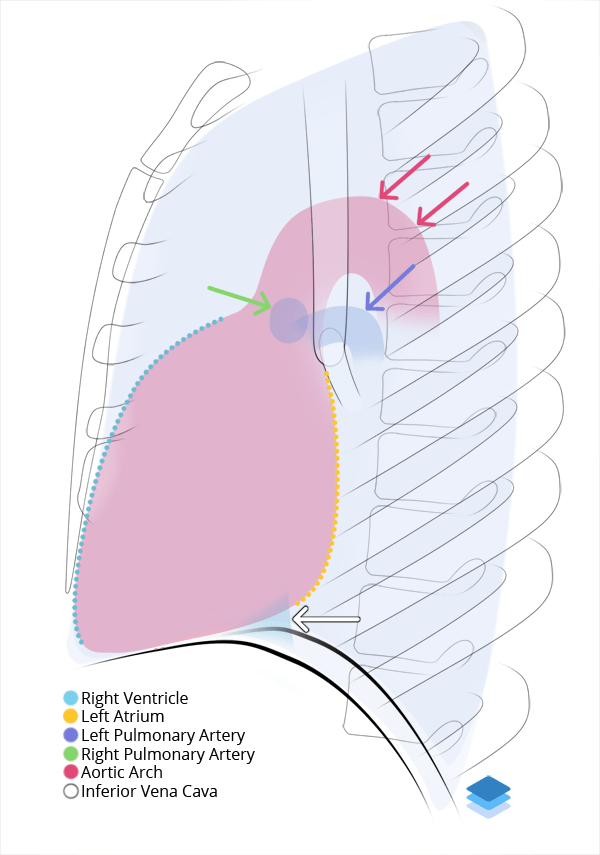

Labelled radiographs and CT/MRI series teaching anatomy with a level of detail appropriate for medical students and junior residents.

Chest

Chest

Chest radiograph & CT anatomy

Chest

Chest

Chest radiograph & CT anatomy